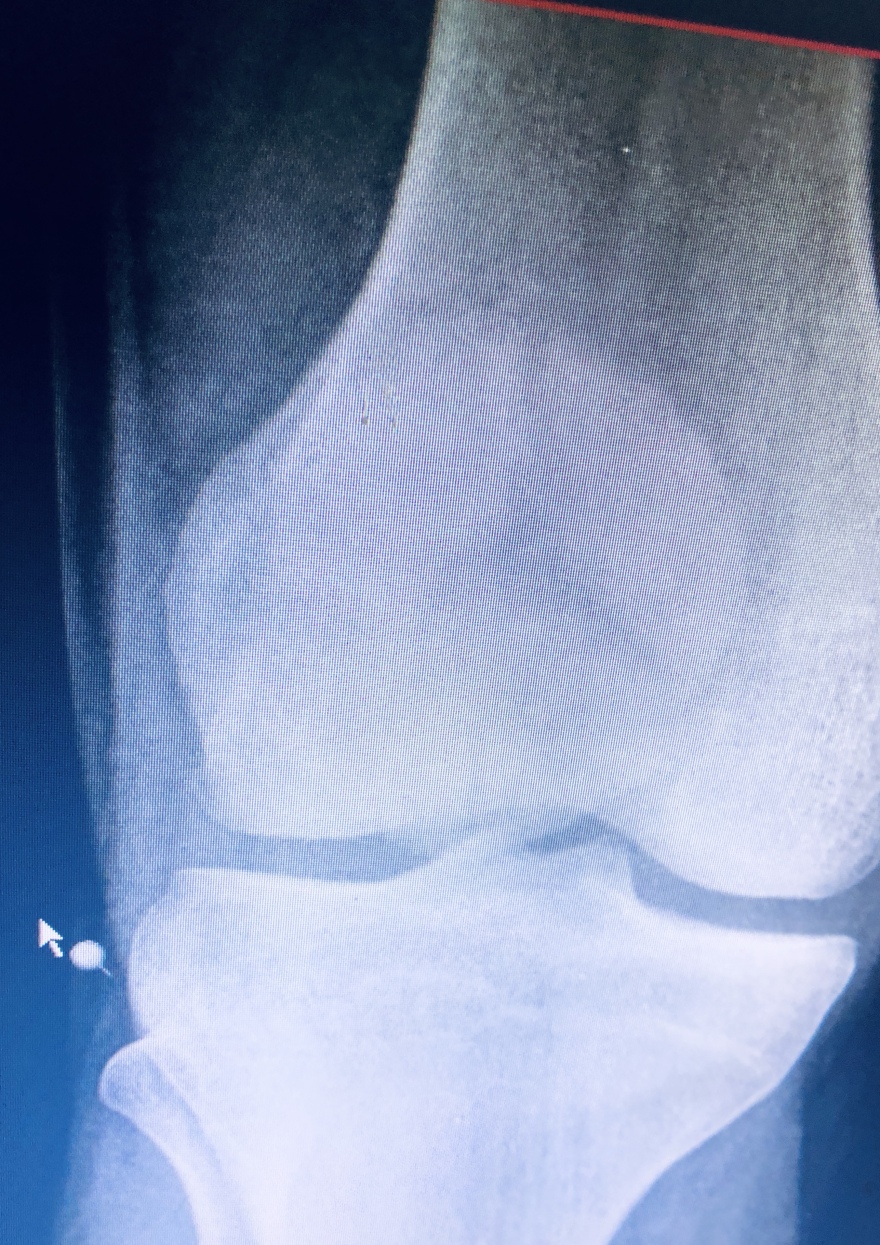

Παρακάτω φαίνεται το αποτελέσμα της έμβασης που είναι η αποκατάσταση του εκτατικού μηχανισμού του γόνατος , της αρθρικής επιφάνειας της επιγονατίδας και του χόνδρου που την καλύπτει , σημαντικοί παράμετροι για την σωστή και ανώδυνη λειτουργεία του γόνατος μελλοντικά.

Δείτε ακτινογραφίες μετά την επέμβαση: